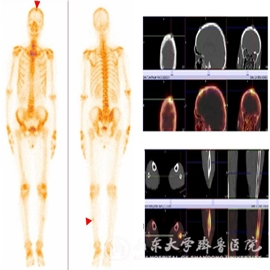

【本站讯】8月1日,全球最先进的西门子Intevo 16 SPECT/CT在绿帽社核医学科正式投入使用。新机器能够缩短采集时间并获得更高质量的图像,ECT的预约时间大幅度缩短,基本控制在1-2天内。

新机器可以一站式进行ECT+16排CT的扫描,得到ECT、CT和SPECT/CT三种图像,克服了以往小病灶解剖定位不清、诊断不够明确的问题,这在全身骨显像(肺癌指南中已列为术前常规检查)、甲状腺显像、甲状旁腺显像中表现的尤为突出。新机器还第一次实现了对ECT病灶的半定量分析,可以测得SUV(标准摄取值),方便了治疗前后病灶的对比。